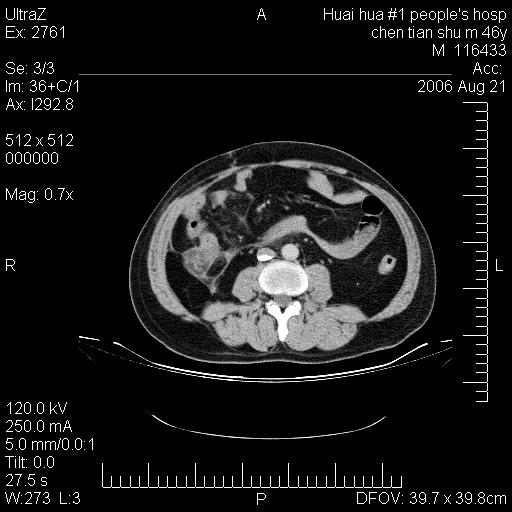

患者,男,46y。腹痛2月,消瘦。

十二指肠水平段占位,考虑间质瘤或平滑肌瘤。

肿块较大,腹膜后占位,境界欠清,周边脂肪密度较高呈条状影,有没有脂肪肉瘤可能,

缺少完整的三期图像。考虑肠系膜脂膜炎mp(肿块型)。

鉴别:间质瘤(这么大而无囊变不可思议)、平滑肌瘤/肉瘤、淋巴瘤、类癌,脂肪类肿瘤、转移瘤等。

十二指肠水平段占位,考虑间质瘤。

首先考虑小肠间质瘤。

十二指肠水平段软组织密度占位,考虑间质瘤可能性大。

腹膜后占位,境界欠清,考虑来源于十二指肠病变,间质瘤或平滑肌肉瘤可能性大。建议活检。

手术病理结果:原发性小肠恶性淋巴瘤(primary gastrointestinal lymphoma,pgil)是原发于胃肠的淋巴网织系统的恶性肿瘤,在结外淋巴瘤中居第一位,该病少见,临床无特异性,诊断困难,术前主要依靠影像学诊断。胃肠道本身具有较丰富的淋巴组织,因而胃肠原发性淋巴瘤是结外淋巴瘤最常见的部位,文献报道约占胃肠道恶性肿瘤的1%~4%,其中胃约占50%~70%,小肠约占35%~70%,结肠约占4%~6%。影像检查在pgil的诊断及分期中有重要的作用,ct是很有价值的检查方法。

胃肠淋巴瘤病理特点:胃肠道原发性淋巴瘤起源于胃肠壁固有层和黏膜下层的淋巴组织即胃肠粘膜相关淋巴组织(malt),多为粘膜相关淋巴瘤。病理上通常为非霍奇金淋巴瘤,且决大多数来源于b淋巴细胞,很少见于霍奇金淋巴瘤。胃肠原发淋巴瘤比胃肠道癌的发病率要低的多,最常见于胃,其病因可能跟幽门螺杆菌感染有关。幽门螺杆菌能引起胃粘膜损害,引起炎性及免疫反应,淋巴细胞聚集并形成滤泡,可影响胃的正常生理功能,导致胃淋巴瘤的发生。单纯性小肠淋巴瘤是常见好发于回盲末端,受累的肠段较长,可单发、多发,甚至累及整个小肠。原发性大肠淋巴瘤罕见,以直肠和盲肠最多见。病变大体观可表现为胃肠腔内外的肿块,也可表现为从黏膜下到浆膜面肠壁的纵向浸润,并且常常伴有肠系膜淋巴结肿大。任何情况下,肿瘤几乎总是导致一定程度的肠壁增厚,可对称或不对称,病变与正常组织间常无明确分界,肠腔可狭窄、正常或动脉瘤样扩张,后者主要是肿瘤在肠壁内浸润,破坏肠壁内植物神经丛所致。以上改变成为ct检测病变的病理基础。

肠道淋巴瘤的ct表现分为4类

1) 壁内浸润型, (2)多发结节型, (3)肠系膜受累伴腔外肿块型(本型就是),(4)肿块型。